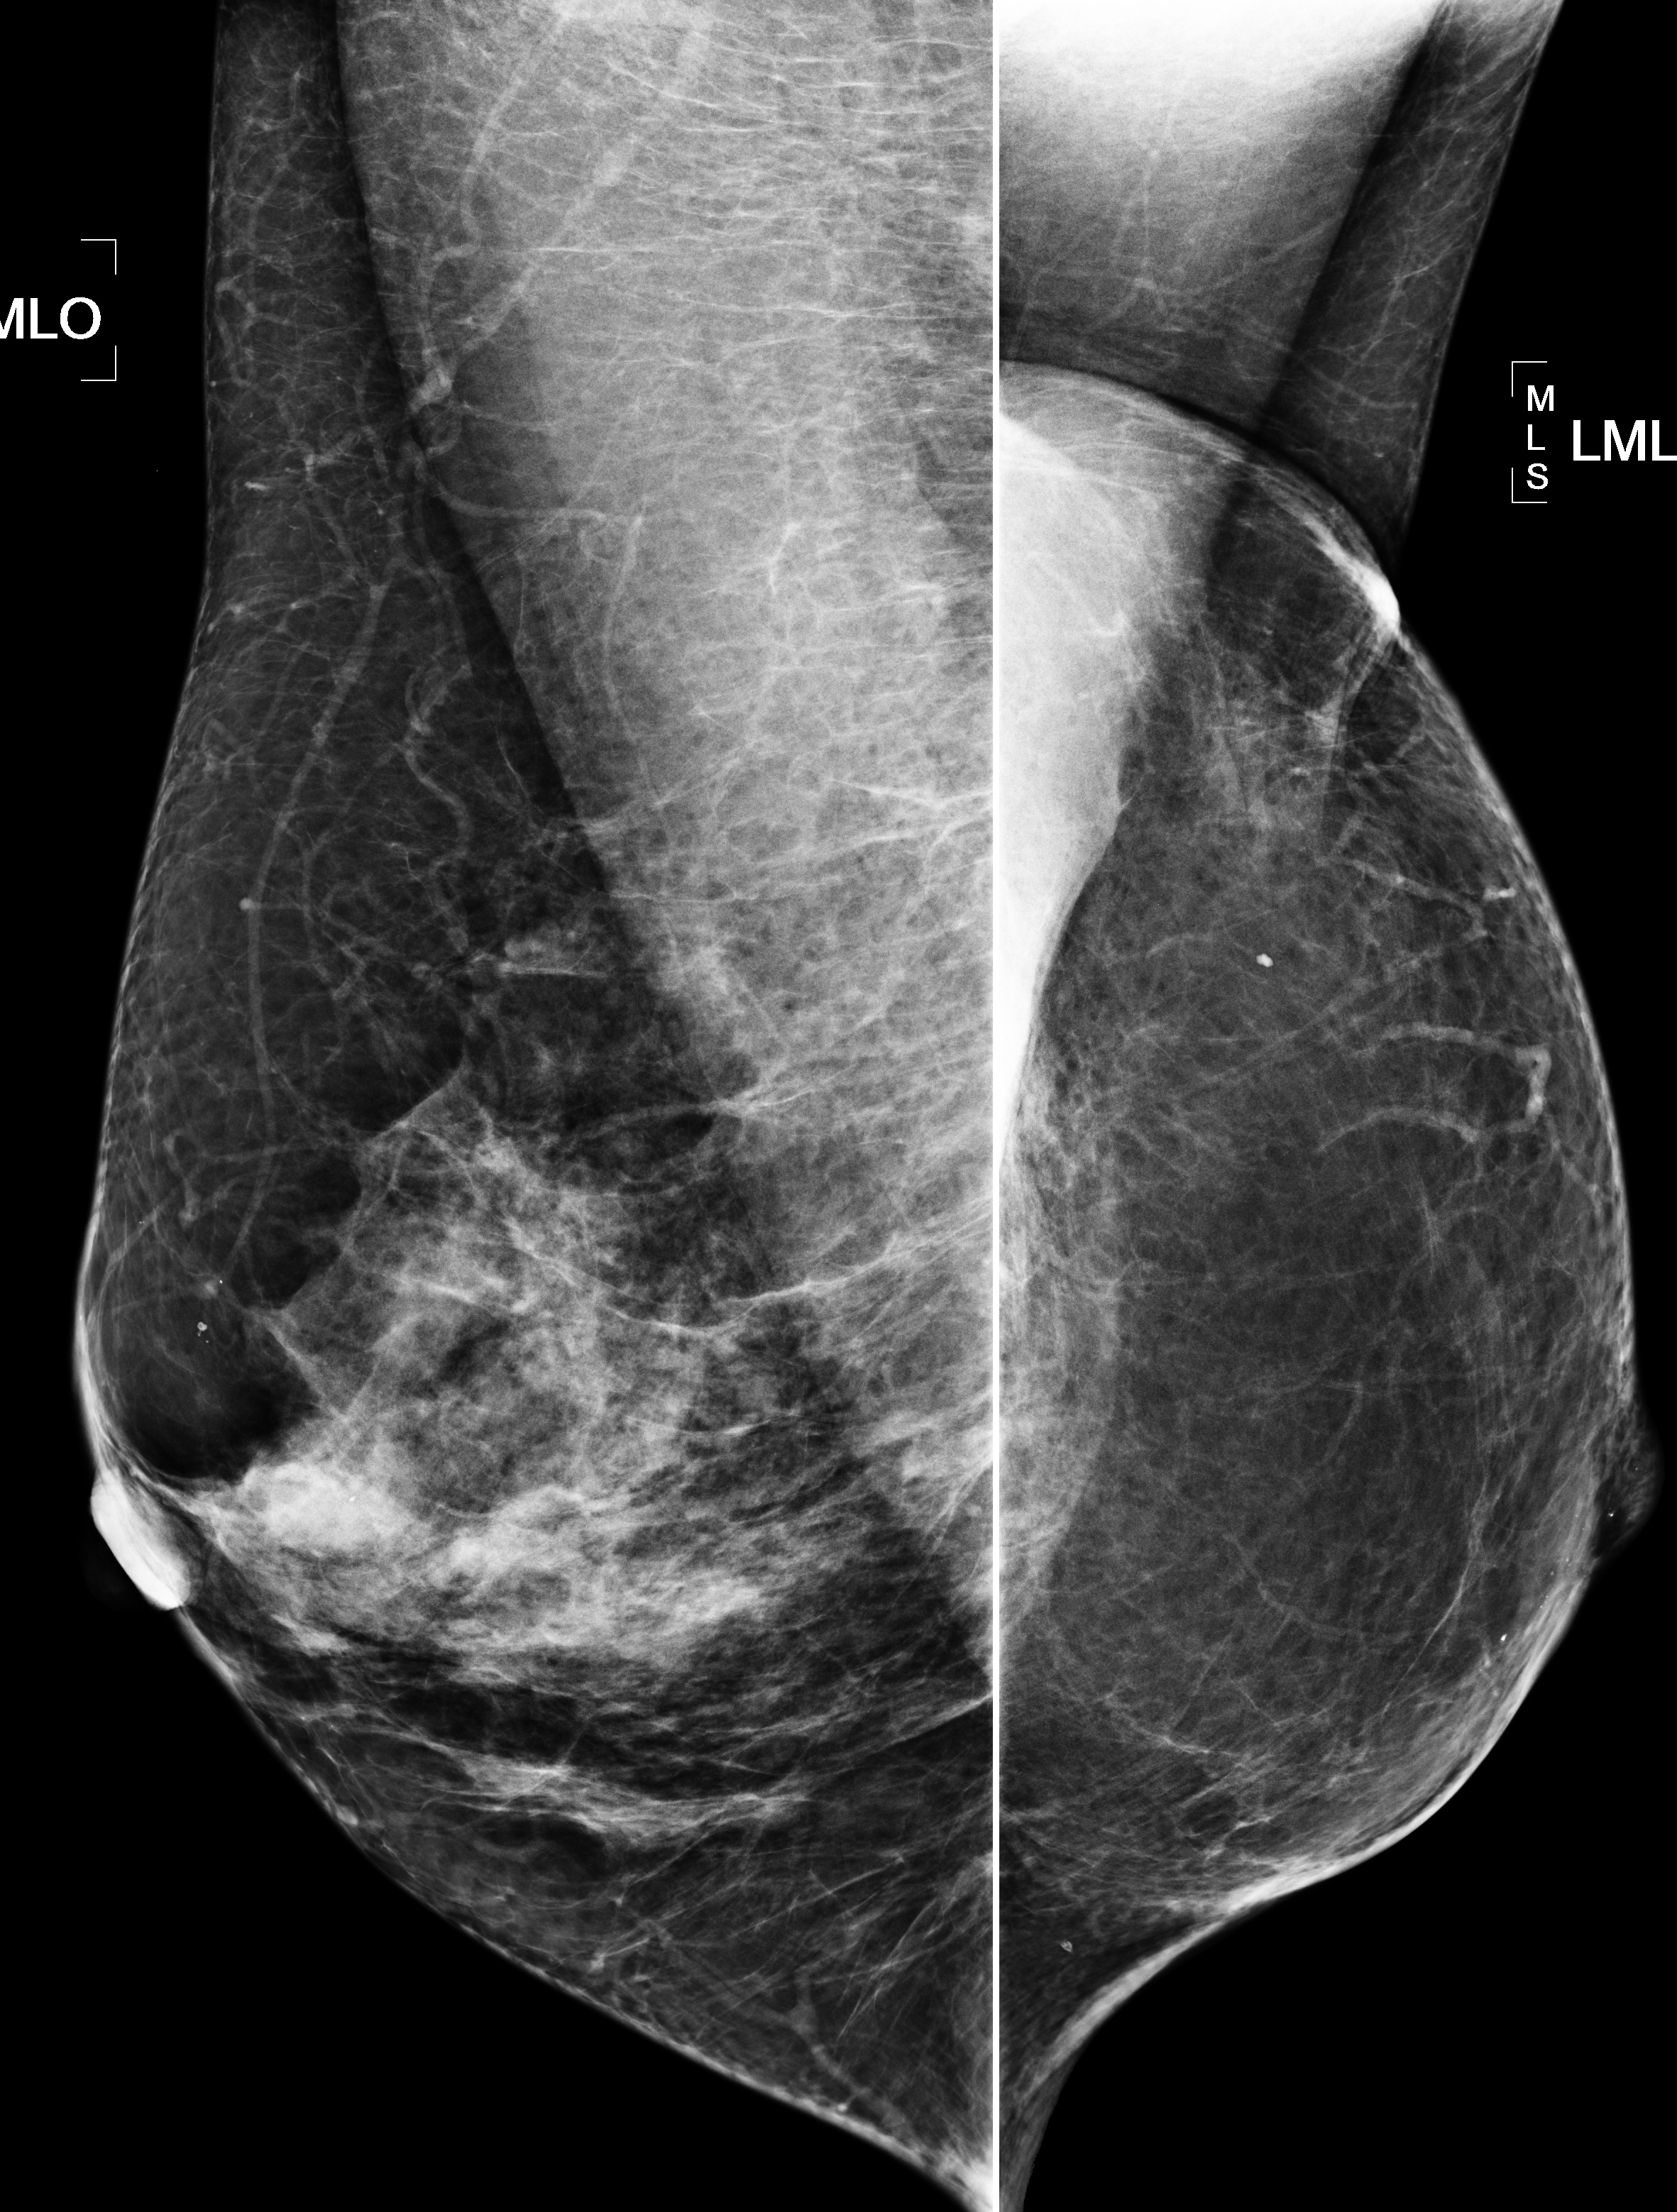

◂Breast Anatomy